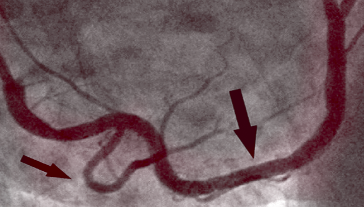

NAKON TERAPIJE

Na slici desno vidimo očišćenu desnu koronarnu arteriju već bez tragova kalcificiranog aterosklerotskog plaka kod istog pacijenta nakon 1. mjeseca terapije. Nema smrtonosnih naslaga kolesterola. Krv teče slobodno, opskrbljujući kisikom sve organe.

example after 2